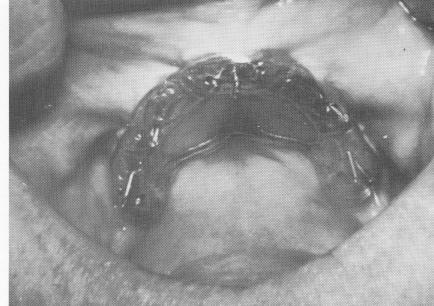

Fig. 10-225. The template was held in position while the pins were individually driven through the holes.

Fig. 10-226. The pins were secured to the template and the template was secured to the fibromucosal tissue by fastening the pins with cold cure acrylic.

2 Template held in position while dental pins driven through the holes